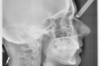

Jeune adulte traitée en technique linguale

E-intermédiaire 1